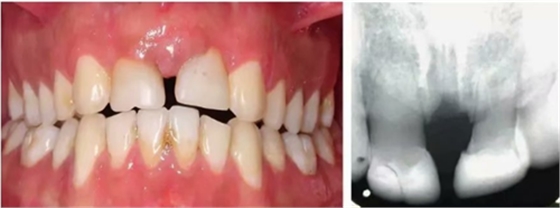

六年和十三年的隨訪顯示移植牙的情況是正常的。移植牙在臨床上是有活力的,影像學(xué)是正常的,沒(méi)有出現(xiàn)髓腔鈣化,也沒(méi)有根骨粘連或牙根吸收的跡象和癥狀(圖7和圖8)。雖然移植牙的牙周膜和牙髓活力都是正常的,但是他們的牙根發(fā)育和冠/根比并不相似。移植牙與鄰牙的牙槽嵴高度相同。

然而,由于移植牙之間較大的間隙,中線處存在吸收的區(qū)域。年齡增長(zhǎng)之后可以進(jìn)行口腔修復(fù)治療或牙周美學(xué)手術(shù)。

【病例分享】上頜中切牙區(qū)外傷的自體移植和正畸治療

圖7. 6年隨訪口內(nèi)照及影像學(xué)檢查

圖8. 13年隨訪口內(nèi)照及影像學(xué)檢查